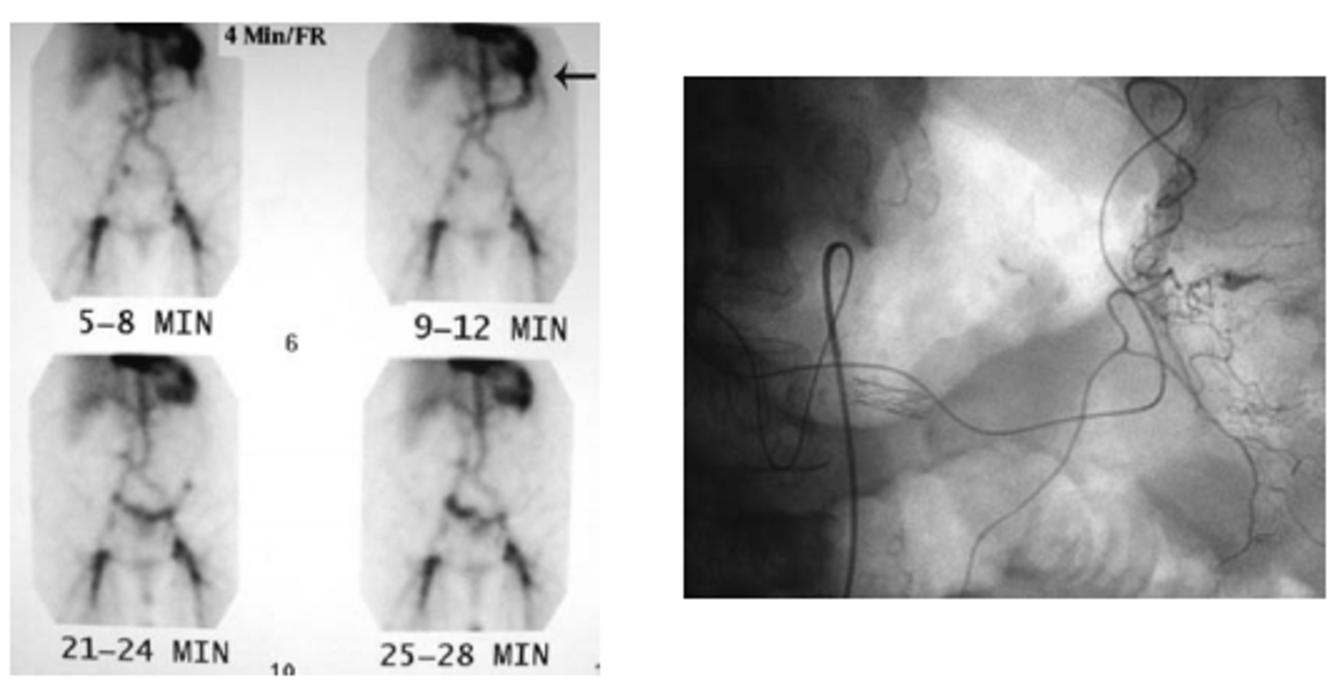

colonic hemorrhage at splenic flexure

A tagged RBC study demonstrated uptake with migration in the expected region of the left colon nearthe splenic flexure (Fig. 1-1). The patient was then referred urgently for mesenteric angiography.

contrast extravasation from a middle colic branch supplying the splenic flexure.